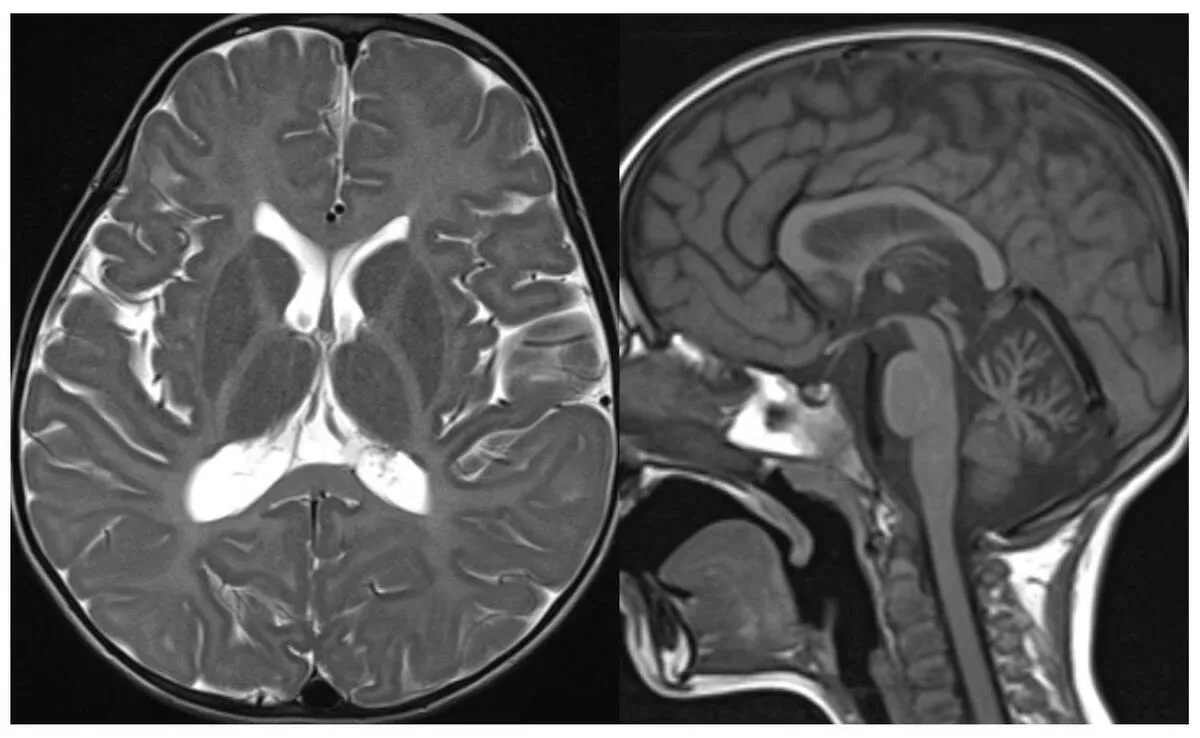

TEHRAN (ANA)- Physical fitness since childhood is associated with cerebellar grey matter volume in adolescents and a recent study conducted at the University of Jyväskylä and the University of Eastern Finland showed that those who were stronger, faster and more agile, in other words, had better neuromuscular fitness since childhood, had larger Crus I grey matter volume in adolescence.

Despite the importance of the developing cerebellum on cognition and learning, the associations between physical fitness and cerebellar volume in adolescents have remained unclear. This study examined the associations of physical fitness with grey matter volume of cerebellar lobules related to cognition in adolescents, and whether these associations differed between females and males. The study was published in the Scandinavian Journal of Medicine and Science in Sports.

Those adolescents with better neuromuscular fitness since childhood had larger Crus I grey matter volume. However, adolescents with better cardiorespiratory fitness had smaller total cerebellar grey matter volume. Moreover, males with better neuromuscular fitness since childhood had smaller Crus II grey matter volume.

Cardiorespiratory fitness was assessed by maximal ramp test on a cycle ergometer, muscular strength with standing long jump, speed-agility with the 10 x 5 m shuttle-run test, coordination with the Box and Block Test and neuromuscular fitness as the sum of standing long jump, Box and Block Test and shuttle-run test z-scores. Cerebellar volumes were assessed by magnetic resonance imaging.